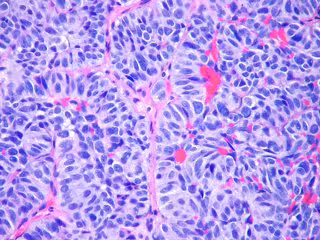

FLICKR/PULMONARY PATHOLOGY/ CC BY-SA 2.0 - Archivo

Las células tumorales circulantes (CTC) son células cancerosas que dejan un tumor primario y entran en el torrente sanguíneo, en su camino hacia la 'siembra' de metástasis a distancia. Estas llamadas CTC se pueden encontrar en la sangre de pacientes como células individuales o grupos de células.